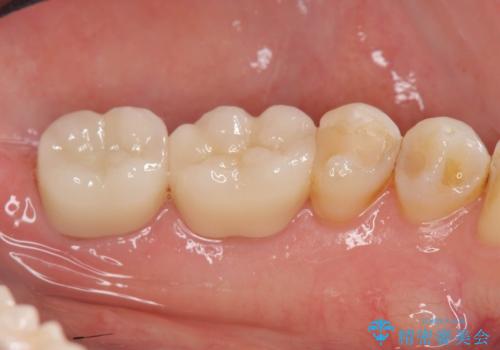

天然歯のような白さのセラミッククラウンで、歯本来の審美性を回復することができました。